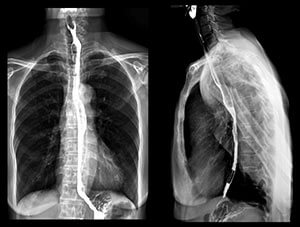

КТ може допомогти виявити захворювання стравоходу кількома способами. По-перше, КТ може виявити аномалії в стравоході, такі як пухлини, стриктури (звуження) або запалення. Зображення, отримані за допомогою КТ, можуть також показати, чи поширилася пухлина на сусідні лімфатичні вузли або органи, що може допомогти лікарям визначити стадію раку. Крім того, КТ може виявити інші захворювання, які можуть бути причиною симптомів пацієнта, такі як грижа стравохідного отвору діафрагми або виразка.

На закінчення, КТ є цінним інструментом для виявлення захворювань стравоходу. Створюючи детальні зображення внутрішньої частини тіла, вона може допомогти лікарям виявити аномалії в стравоході та навколишніх тканинах. Пацієнти, які проходять КТ, повинні знати про підготовку, необхідну для проведення дослідження, а також про потенційні ризики та ускладнення, пов'язані з ним. Тісно співпрацюючи зі своєю медичною командою, пацієнти можуть гарантувати, що вони отримають найточніший діагноз і відповідне лікування для свого стану.